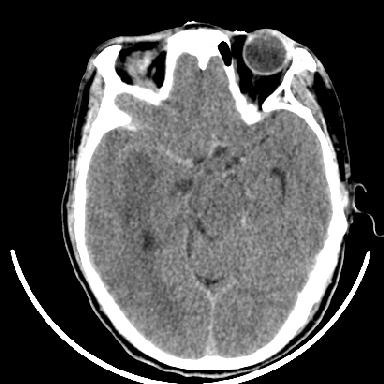

标题: CT6056:脑出血(血管畸形?) [打印本页]

标题: CT6056:脑出血(血管畸形?)

m 40突发头痛左侧偏瘫3小时

但脑出血早期做增强是不是有点太冒险了?

术中抽出40ml陈旧血液,血肿底部似见一条索血管影